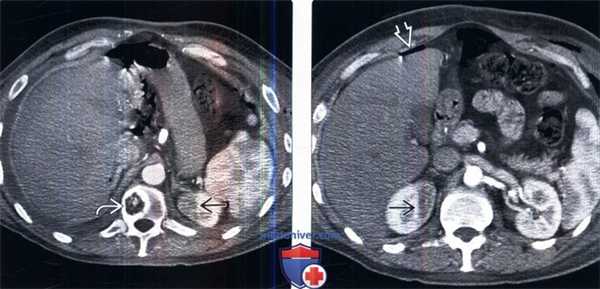

(Слева) Мужчина средних лет после недавней резекции рака толстой кишки, прошедший курс радиотерапии по поводу метастазов в позвоночнике. На КТ с контрастированием, в аксиальном срезе в левой почке определяется гиподенсная зона с четкими границами. Обратите внимание на наличие метастазов в позвоночном столбе, которые были мишенью радиотерапии.

(Справа) На более каудальном срезе, у этого же пациента определяются признаки радиационного нефрита правой почки. Обратите внимание на наличие свободного воздуха в связи с недавней лапаротомией.